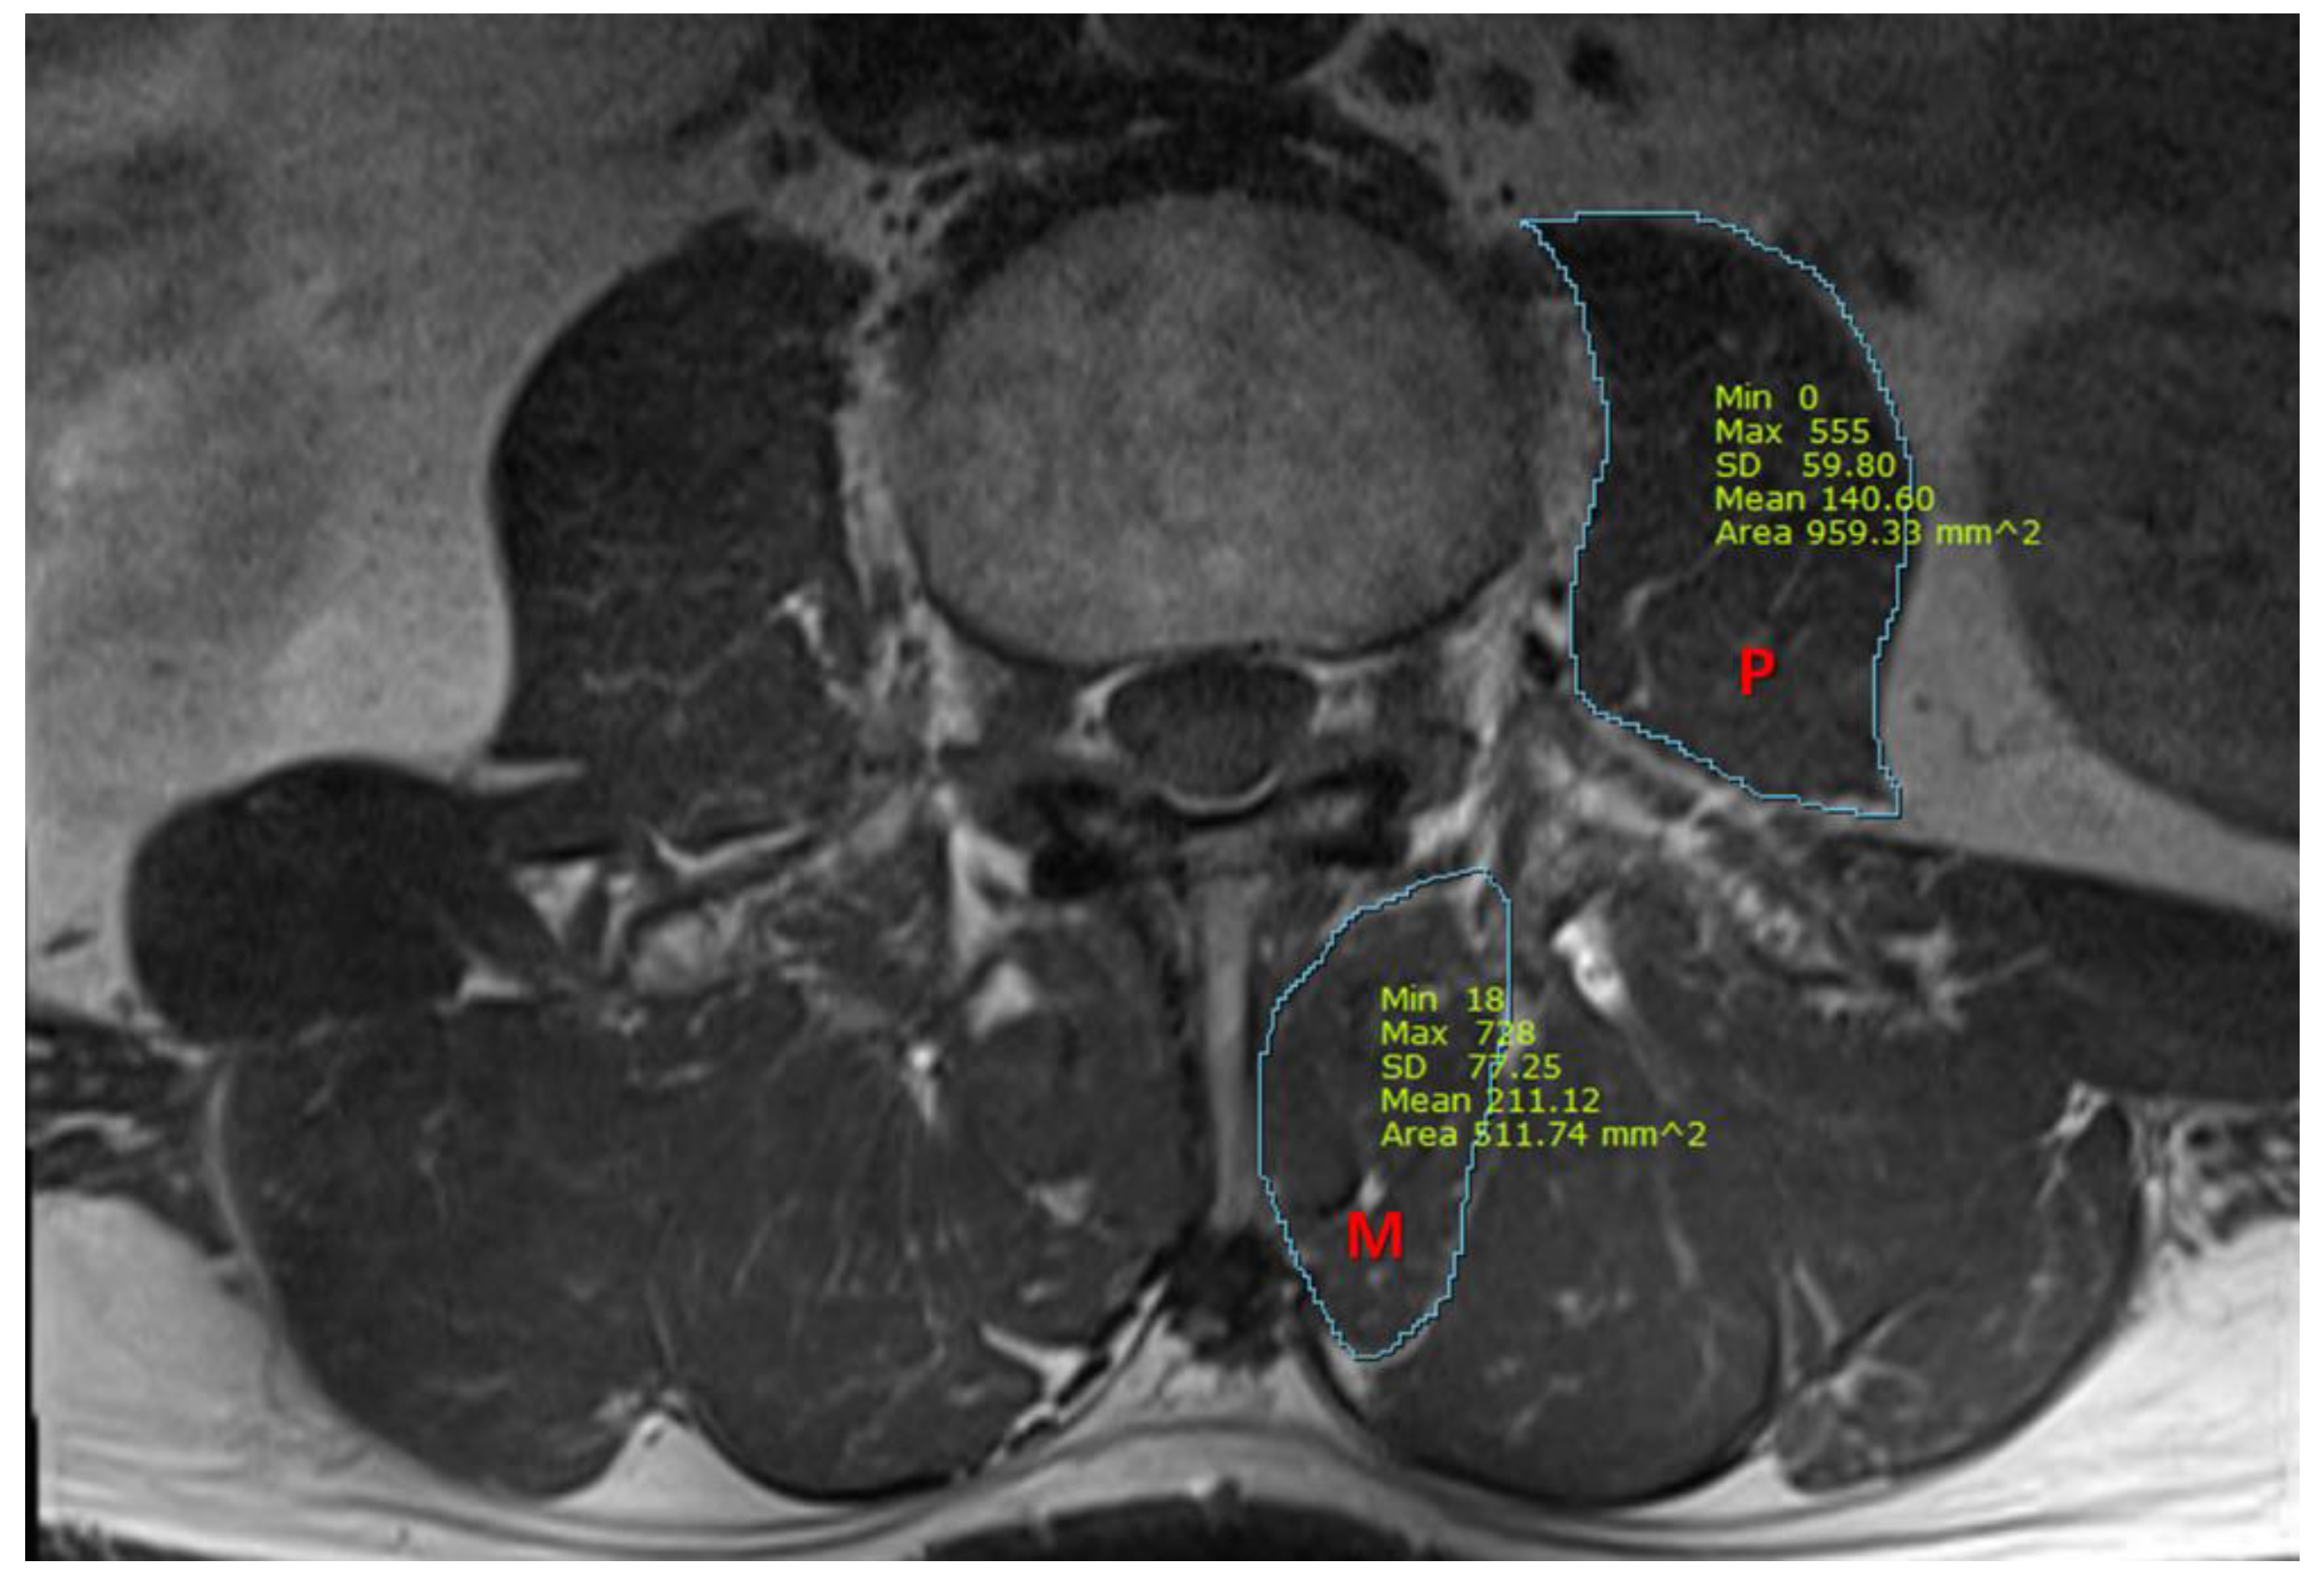

| CSA of psoas (mm2) | |||

| Male | 1147.3 ± 119.8 | 539.9 ± 145.5 | <0.001 * |

| Female | 879.4 ± 219.2 | 619.9 ± 175.1 | 0.020 * |

| CSA of multifidus (mm2) | |||

| Male | 676.0 (540.5–804.1) | 398.3 (324.4–510.6) | <0.001 § |

| Female | 575.1 ± 178.0 | 459.3 ± 93.4 | 0.146 |